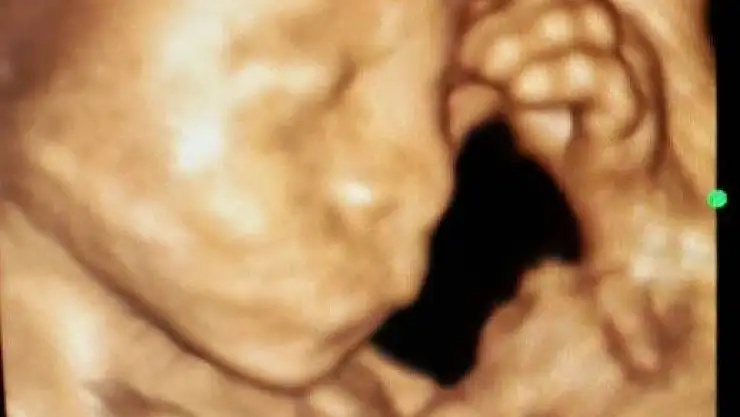

Anne karnında düşünen bebek

Konya’da 23 haftalık bebeğinin anne karnında elini başına koyarak düşünen hali ultrason ile kaydedildi.

Konya’nın Ereğli ilçesinde bir anne adayının kontrol edilen 23 haftalık kız bebeği 4 boyutlu ultrason cihazında elini başına koyarak düşünürken görüldü. Gördüğü manzara karşısında şaşıran Kadın Doğum Uzmanı Op. Dr. Kadriye Turgut bu anı ölümsüzleştirerek fotoğraf olarak kaydetti.

Anne karnında bebeğin annenin yaşadığı mutluluğu, sevinci, üzüntüyü hissediyor olarak bilinmesi, kaydedilen bu fotoğraf ile 'acaba bebek annesinden mi etkileniyor' düşüncesini akıllara getirdi.